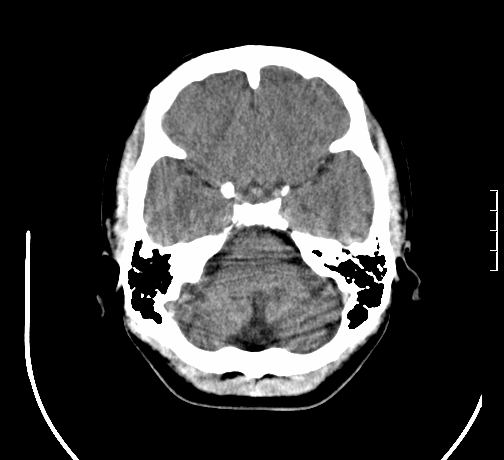

女,28岁,幼时有癫痫,常有发作,服药后可几月不发作,走路不稳3-4月,加重一月。

小脑发育畸形?

小脑萎缩。

考虑小脑发育不良,建议mri检查。

患者出现走路不稳是近几个月的事,而癫痫则有幼时就有,常发,则会常服药,癫痫药可引起小脑综合症,小脑萎缩,而小脑发育不良的主要症状不是癫痫

考虑癫痫,长期间断发服抗癫药,导致小脑综合症,小脑萎缩

不知现在还有没有癫痫,应该另有致痫灶,进一步检查。

考虑小脑发育不良伴小脑萎缩,建议mri检查。

小脑萎缩,原因待查,建议mri检查。

考虑小脑发育不良伴小脑萎缩,建议mri检查

考虑药物性小脑萎缩